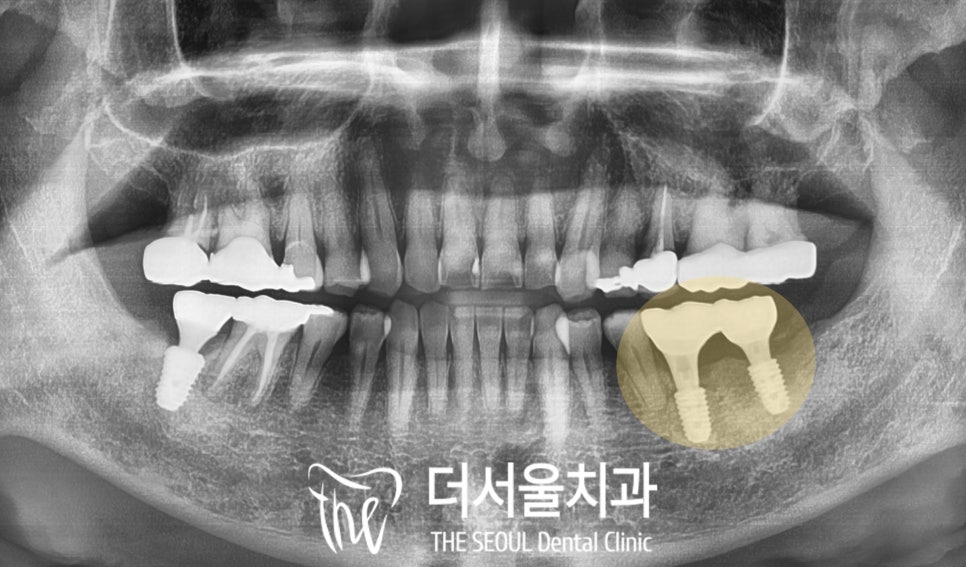

왼쪽 아래 구치부 모든 보철까지

세팅 완료된 모습입니다.

어금니 교합력을 잘 버틸 수 있도록

브릿지로 제작하였으며

대합치와 어색하거나

불편한 부분은 없는지도

확인해 드렸습니다.